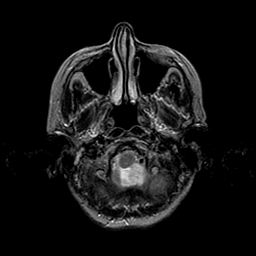

Metastatic Adenocarcinoma of the Colon: T2-weighted MR -- Slice #3

[Home][Help][Clinical] Slice 3